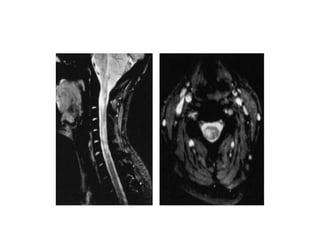

Spinal cord.

• MS lesions of the spinal cord are usually found in

combination with lesions in the brain; however,

5% to 24% of cases can be found in isolation

• MR studies have shown that cord abnormalities

may be found in approximately 75% of MS

patients and in an even higher proportion of

patients with spinal cord symptoms

• Most lesions are found in the cervical region

• Axial T2-weighted images demonstrate the

typical peripheral location of MS lesions commonly

the dorsolateral aspect of the cord, where pial veins

are adjacent to white matter .

• Involvement of both gray and white matter by MS

plaques can be seen.

• Gadolinium contrast administration frequently

demonstrates enhancement of acute spinal cord

lesion

• The most typical enhancement pattern in

demyelinating spinal cord lesions is a peripheral

ringlike enhancement, although this is not always

seen

• Enhancing MS plaques can be virtually

indistinguishable from neoplastic lesions and other

inflammatory lesions of the spinal cord particularly

when the spinal cord is enlarged due to edema.

• Therefore, clinical correlation and often serial

follow-up scanning are necessary to formulate a

specific diagnosis,